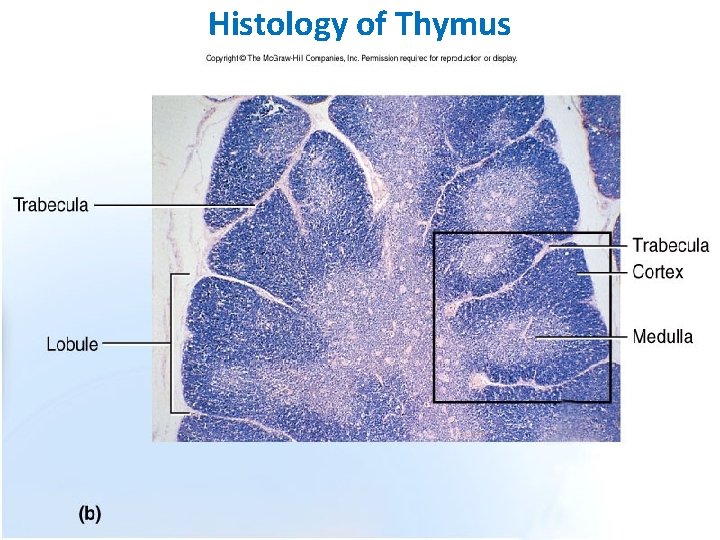

Thymus is the only discrete central lymphoid organ in humans. It produces only T lymphocyte precursors and has no lymphoid nodules. Its reticular cells derive from endoderm and produce no reticular fibers. It is the only organ containing Hassall’s corpuscles. Its age-dependent structural atrophy or involution is also unique among lymphoid organs. 2 lobes are joined and covered by a thin loose connective tissue capsule that penetrates the lobes as septa, dividing each lobe into incomplete lobules. Cortex. This is the dark-staining periphery of each lobule. Small lymphocytes predominate

Medulla. In effect, each thymic lobe has a single medulla that extends into the core of each of the lobules. The light staining of the medulla reflects the presence of more epithelial reticular cells and fewer lymphocytes than in the cortex. The spheric Hassall’s corpuscles (30 -150 m in diameter) are composed of concentric layers of flattened epithelial reticular cells. With age, cells in the core of the corpuscles may die and calcify. Functions: 1. T lymphocyte production. 2. Blood -thymus barrier. 3. Production hormone - thymosin

Histology of Thymus 40

Thymus • • n Hassal’s Corpuscles Capsule Lobules Cortex Medulla